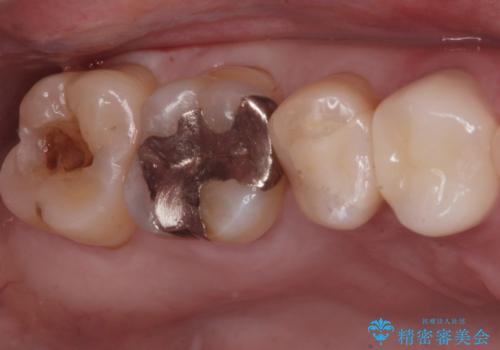

- 口を開けた時、銀の詰め物が目立つとのことで来院。

拡大鏡下で詰め物を外し、う蝕がない事を確認して、セラミック(e-maxインレー)で治療を行いました。

銀の詰め物は歯質との間の隙間ができやすく

虫歯の再発リスクが高いです。

セラミックの詰め物(e-maxインレー)は歯質との隙間ができにくく

虫歯の再発リスクが低くなります。

口を開けた時、銀歯が目立たなくなり、大変満足して頂けました。